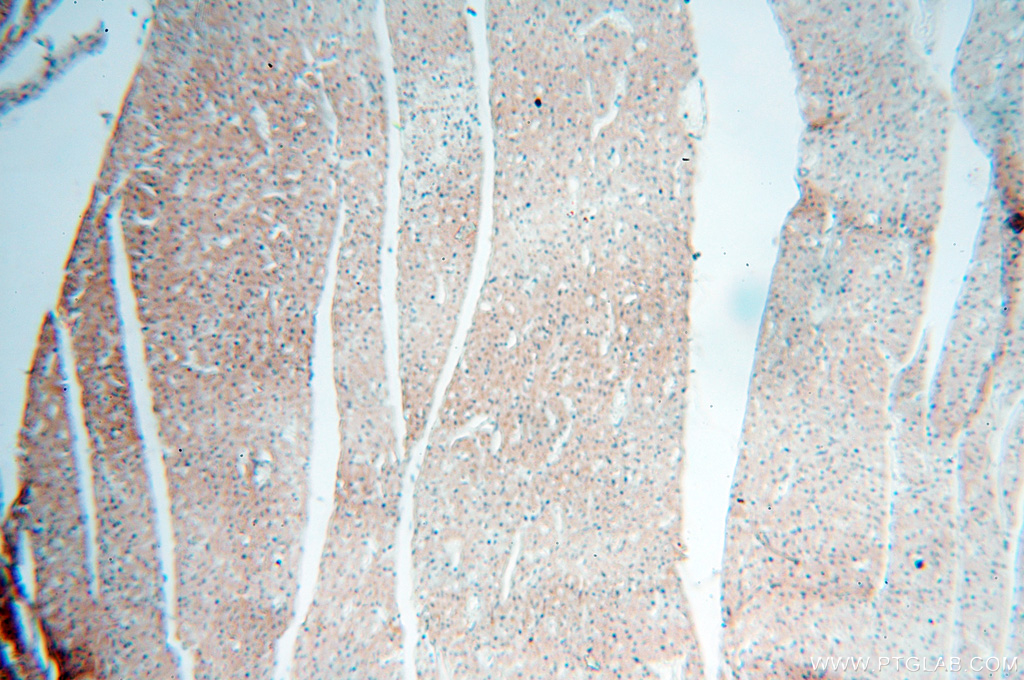

| Positive IHC detected in | human lung tissue, human brain tissue, human heart tissue Note: suggested antigen retrieval with TE buffer pH 9.0; (*) Alternatively, antigen retrieval may be performed with citrate buffer pH 6.0 |

| Immunohistochemistry (IHC) | IHC : 1:20-1:200 |